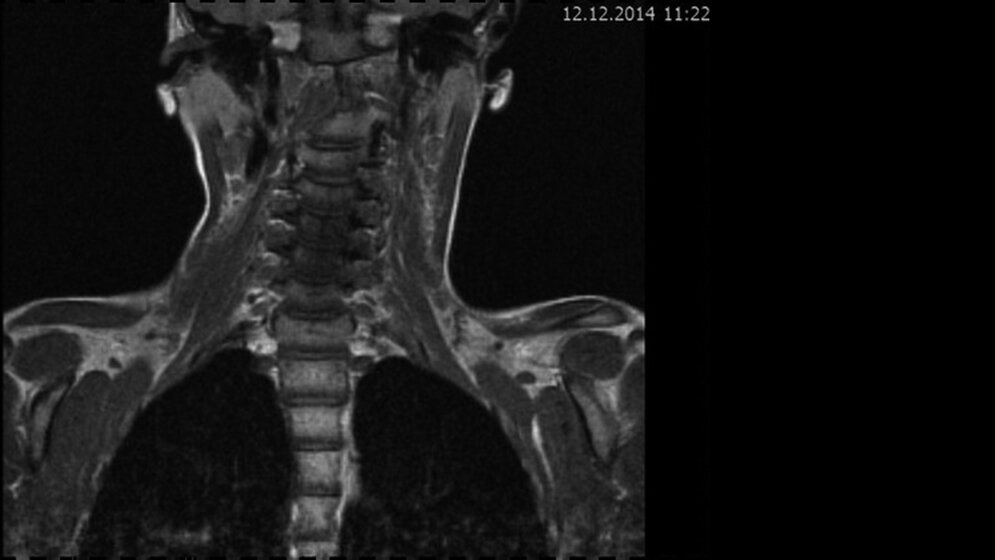

Das Fallbeispiel 1 zeigt im Verlauf eine Komplikation bei einer Arnold-Chiari-Malformation Typ 1 bei einem zum Zeitpunkt der Erstdiagnose 12-jährigen Jungen. Dieser hatte im Sportunterricht einen schweren Medizinball geköpft und ein Stauchungs-trauma der Halswirbelsäule erlitten. Nach anfänglich symptomatischer frustraner Therapie wurde er vom behandelnden Orthopäden zur MRT der HWS überwiesen. Es wurde eine Streckfehlhaltung und flachbogig rechtskonvexe Skoliose diagnostiziert, klinisch bestand ein Torticollis. Eine knöcherne oder ligamentäre Verletzung wie auch eine Schädigung des Rückenmarks bzw. eine intraspinale Bandscheibendislokation konnten bildmorphologisch ausgeschlossen werden.

Bei dieser Untersuchung wurde übersehen, dass die Kleinhirntonsillen in das Foramen magnum disloziert waren und eine Arnold-Chiari-Malformation mit Erweiterung des 4. Ventrikels und des Aquäduktes inklusive Kleinhirntonsillentiefstand vorlag. Bei zwischenzeitlich auswärtig erfolgtem CT der HWS wurde eine Anlagestörung im kraniozervikalen Übergang beschrieben. Eine Kontrolluntersuchung des Kopfes weitere 4 Monate später dokumentierte neben einem medullären Ödem einen progredienten Tonsillentiefstand, der zur neurochirurgischen Behandlung mit operativer Erweiterung des Foramen magnum führte.